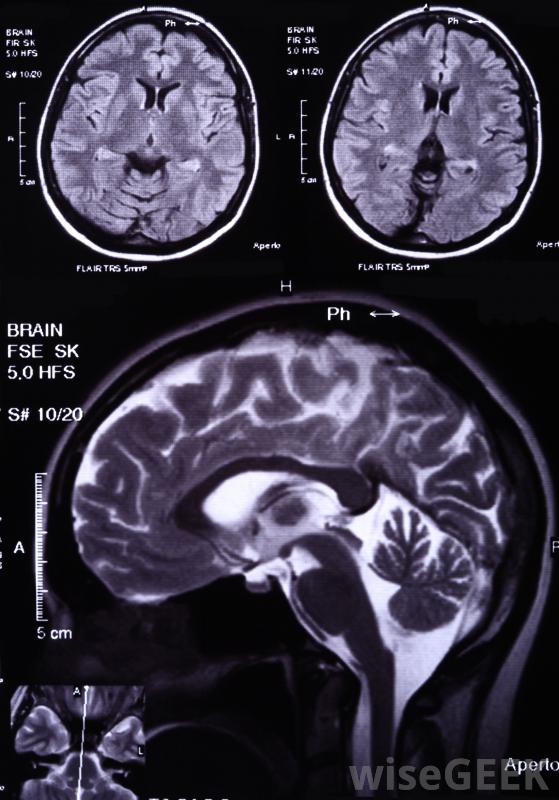

随着肿瘤的生长,患者可能会出现头晕、神志不清和其他神经系统问题。医生可以诊断为胶质母细胞瘤通过医学影像学研究来观察大脑,并对其生长过程进行生物切片以找出它是什么当病理学家检查活检标本时,他或她可以确定哪些类型的细胞参与其中,以及肿瘤的侵袭性有多强。胶质母细胞瘤也被称为IV级星形细胞瘤,指的是肿瘤起源的细胞类型,以及这些肿瘤非常具侵略性的事实

医学影像学研究可用于诊断胶质母细胞瘤脑瘤化疗和放疗有助于延长胶质母细胞瘤患者的寿命。